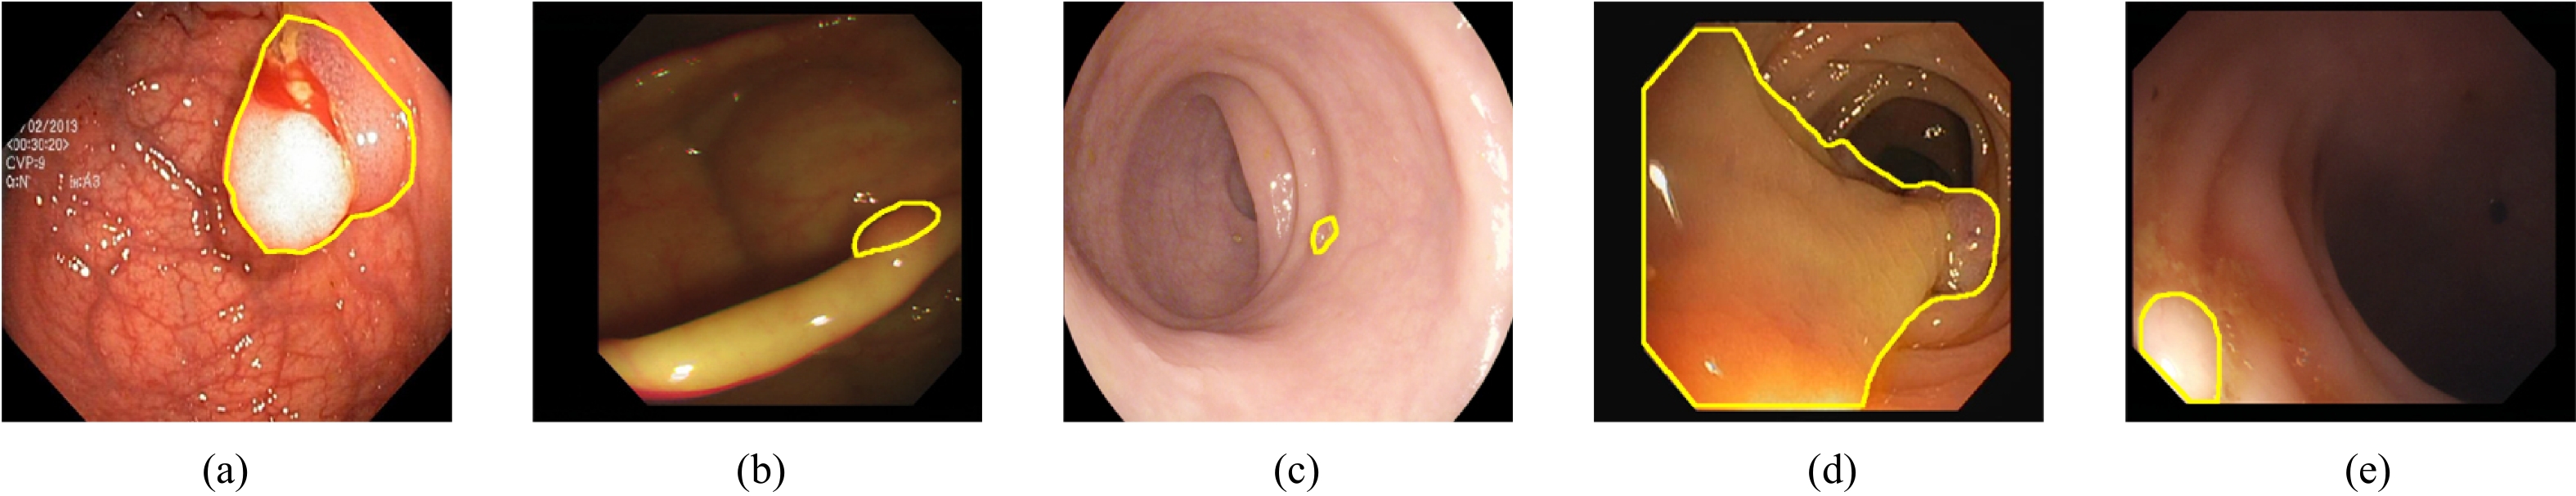

• Colorectal cancer has become a global public health concern. Removing polyps before they become malignant can effectively prevent the onset of colorectal cancer. Currently, multi-receptive field feature extraction and attention mechanisms have achieved significant success in polyp segmentation. However, how to effectively fuse these mechanisms and fully leverage their respective strengths remains an open problem. In this paper, we propose a polyp segmentation network, MFAINet. We design an attention-integrated multi-receptive field feature extraction module (AMFE), which uses layering and multiple weightings to fuse the multi-receptive field feature extraction and attention mechanisms, maximizing the extraction of both global and detailed information from the image. To ensure that the input to AMFE contains richer target feature information, we introduce a multi-layer progressive fusion module (MPF). MPF progressively merges features at each layer, fully integrating contextual information. Finally, we employ the selective fusion module (SFM) to combine the high-level features produced by AMFE, resulting in an accurate polyp segmentation map. To evaluate the learning and generalization capabilities of MFAINet, we conduct experiments on five widely-used public polyp datasets using four evaluation metrics. Notably, our model achieves the best results in nearly all cases.